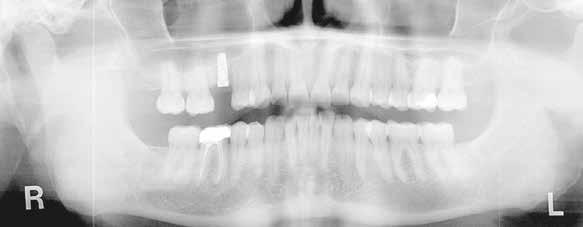

A laboratóriumokban és a fogorvosi rendelőkben mindenki ismeri ezt az esettípust: a páciensnek generalizált parodontitis miatt már több foga is elveszett a felső állcsontban, és kivehető fogsort visel. A tömörebb mandibulacsont eddig jobban bírta a krónikus bakteriális fertőzést, egészen addig, amíg a metszőfog körüli csonthiány túl nagy lett, és a metszőfogat is ki kellett húzni. Ennek az egyetlen résnek köszönhetően a páciens fix restaurációt kért. Az implantátum nem volt kívánatos, és nem is javasolt a krónikus fertőzés, a rossz csontozat és a korlátozott hely miatt. A következő esetpéldában dr. Julio Gomez Paris (Rosario, Argentína), aki fogorvos és fogtechnikus egyben, bemutatja, hogyan lehet ez a fajta eset minimálisan invazív, esztétikus és gazdaságosan megoldható a fogszín szisztematikus és precíz, a VITA 3D-MASTER fogszínkulcs segítségével történő meghatározásával és a hozzáillő VITA YZ ST Multicolor cirkon anyagának használatával (VITA Zahnfabrik, Bad Säckingen Németország).

A 76 éves páciens azért kereste fel a fogorvosi rendelőt, mert észrevette, hogy a 31-es fog kilazult, és az azzal való harapás fájdalmat okozott. Parodontális szondázás és röntgen diagnosztika után egyértelmű volt, hogy a fogat nem érdemes

4. ábra: A 32, 41 és 42 fogak előkészítése hídpillérekként.

megőrizni. Helyi érzéstelenítést követően a fogat eltávolítottuk, és a 42, 41, illetve 42 fogak között keletkezett foghiányt híd megoldással teveztük megoldani a gyógyulási folyamat után. A pontos fogszínmeghatározást és dokumentálást a VITA Linearguide 3D-MASTER segítségével végeztük el annak érdekében, hogy a megfelelő árnyalatú cirkontömböt tudjuk kiválasztani. A fogszínkulcs lehetővé teszi a szisztematikus és gyors fogszínmeghatározást két lépésben. Minden fogszín a világossági értékből, az árnyalatintenzitásból és a színárnyalatból tevődik össze. Emiatt a VITA Valueguide 3D-MASTER segítségével először csak a fogak világosságát, azaz fekete/fehér tulajdonságát állapítjuk meg. A 0-tól 5-ig

terjedő skálán a választás a 2-es árnyalatot mutató pálcára esett, tehát a VITA Chroma/Hueguide 3D Master 2-es csoportban folytattuk a meghatározást. A színárnyalattal (M) és az árnyalatintenzitással (3) kölcsönhatásban végül egy 2M3 fogszín került meghatározásra és fotódokumentálásra.

Cirkónium minden indikációhoz

A VITA YZ cirkon négy áttetszőségi fokozatban kapható (transzlucens, erősen transzlucens, szuper transz -

5. ábra: A monolitikus híd szinterezés után a kiegészítő kontroll modellen.

7. ábra: A cirkóniumhíd két héttel a beragasztás után.

6. ábra: A szuper transzlucens cirkónia VITA YZ ST Multicolor híd incizális nézetben.

lucens és extra transzlucens). A szuper transzlucens, illetve polikromatikus, azaz színátmenetes VITA YZ ST Multicolor cirkont választottuk a teljes anatómikus hídpótláshoz, 1200 MPa 3 pontos hajlítószilárdsági értéke miatt kiválóan alkalmazható hidak készítéséhez. 46%-os áttetszőségével megfelel az anterior fogrégió esztétikai követelményeinek is. Az integrált színátmenetnek és a VITA fogszínkulcshoz való árnyalathűségnek köszönhetően az anyag különösen alkalmas monolitikus helyreállításra is.

1. A megfelelő árnyalat és a természetes színátmenet már adott a tömbben, ami alapkövetelmény egy olyan eljárásnál, amely lehetőleg minimálisan invazív, különösen az alsó állcsont érzékenyebb metszőfogai esetében.

2. Az előkészítést, majd a CEREC Primescan készülékkel történt digitális lenyomatvételt követően a hidat az elvárt erősségű összekötésekkel az inLab 22.0 tervező szoftverrel megterveztük és a CEREC Primemill maró készülékkel legyártottuk (all Dentsply Sirona, Bensheim Germany).

A marás után a restaurációt a VITA ZYRCOMAT 6100 MS (VITA Zahnfabrik) szinterező kemencében fejeztük be.

Árnyalathűség mint a siker kulcsa

A precíz marási eredményeket igazolva kontroll modellt készítettünk additív technológiával. A kromacitás színátmenete és a kiegyensúlyozott transzlucencia a teljes anatómikus hidat karakterizálás nélkül is nagyon természetessé tette, így a VITA AKZENT Plus EFFECT STAINS 05 színezővel csak minimális narancssárga színű karakterizálás történt incizálisan és interproximálisan. Ezt követte a VITA AKZENT Plus GLAZE LT-vel történő felületfinomítás. Megfelelő klinikai bepróbálás után a hidat önkötő cement segítségével be lehetett ragasztani. A fogszín szisztematikus meghatározása és a VITA YZ ST multicolor tömb megfelelő árnyalatban történő kiválasztása megteremtette az alapvető esztétikai feltételeket. Az egyszerre szuper transzlucens és polikromatikus anyag minden esetben a cirkónia lett, amely integrált esztétikájának és szilárdságának köszönhetően gazdaságos és gyors restaurálást tett lehetővé. A páciens elégedett volt, hogy sikerült fix pótlást készíteni, és teljesen elégedett volt új, hézagmentes mosolyával.